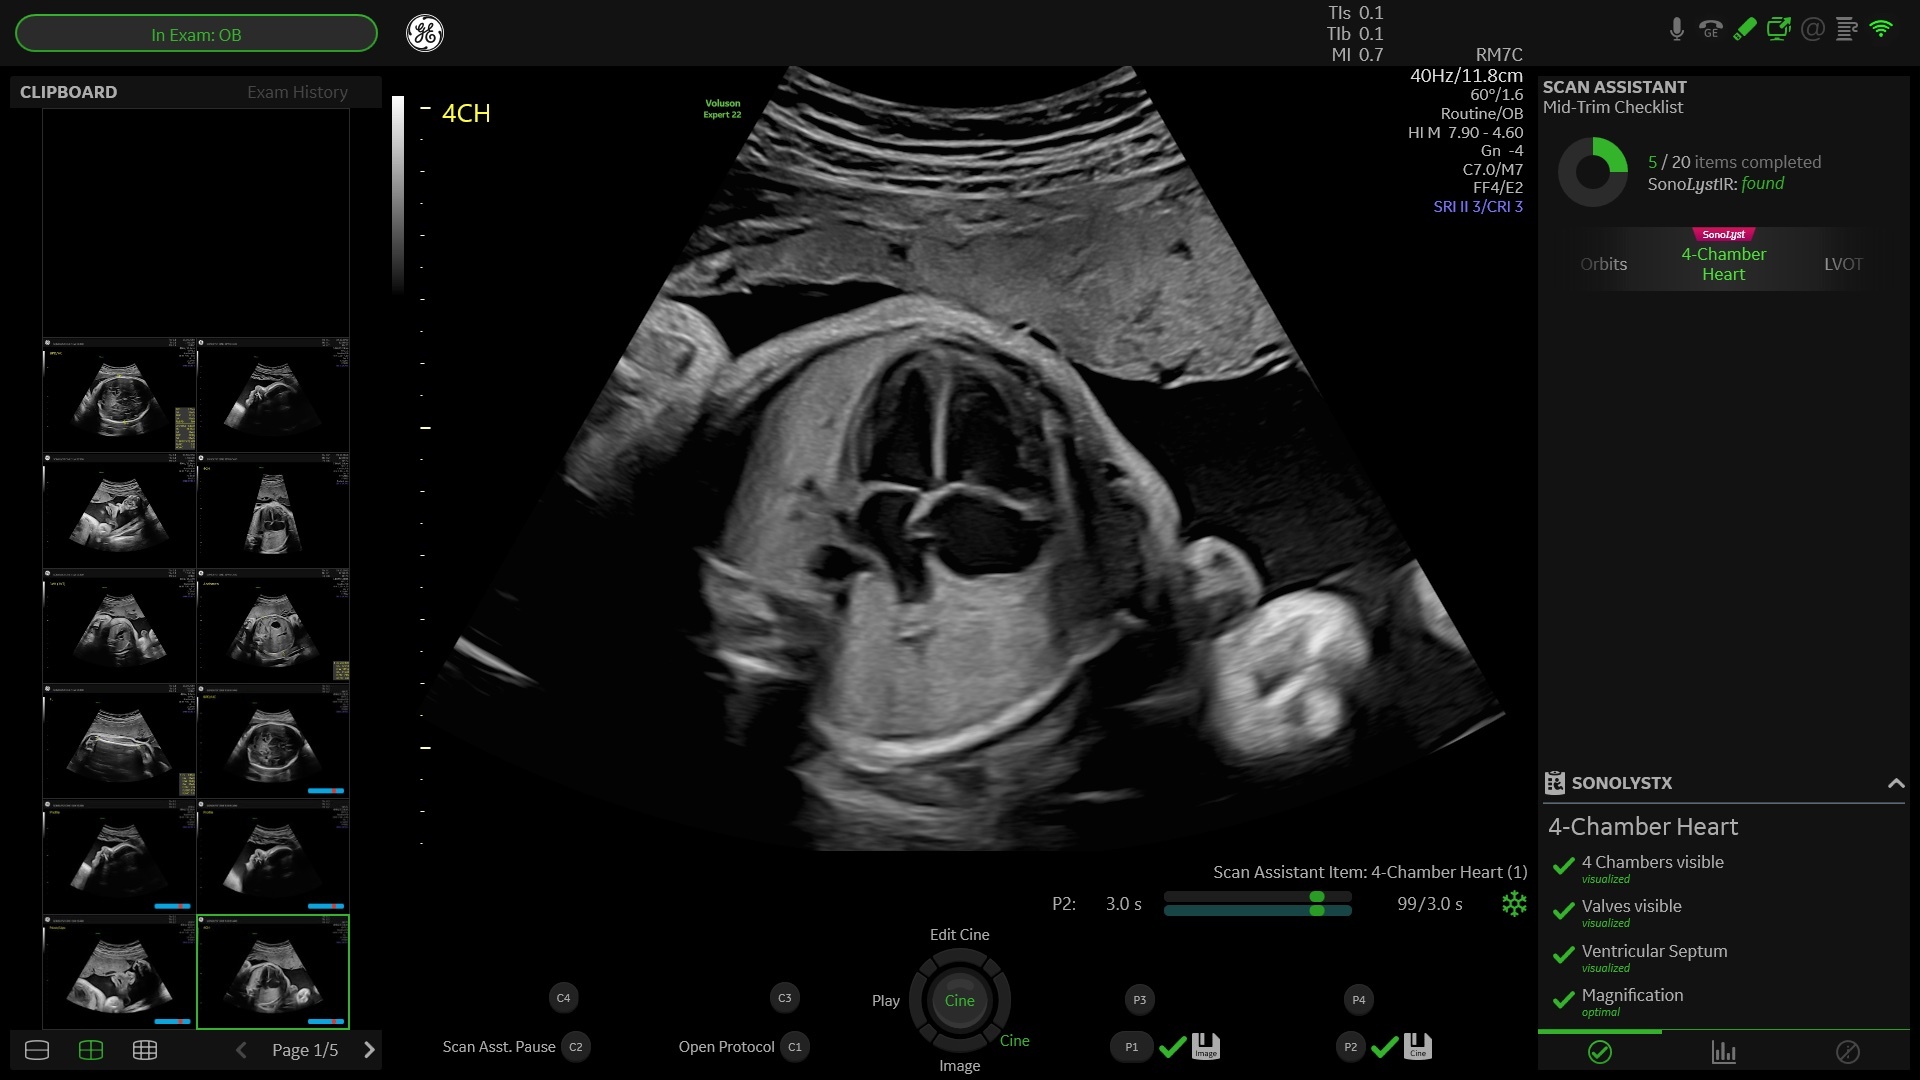

from www.volusonclub.net

Utilizing Fetal Heart Ultrasound for Congenital Heart Disease

Utilizing Fetal Heart Ultrasound for Congenital Heart Disease Heart Ultrasound Pots Pots is defined as the presence of chronic symptoms of orthostatic intolerance (≥6 months) accompanied by an increased heart rate (hr) ≥30 bpm within 10 minutes of assuming an. The symptoms of pots are associated with an. Heart monitoring devices, such as a. 1) to establish working criteria for the diagnosis of postural tachycardia syndrome (pots),. Tests to assess the. Heart Ultrasound Pots.